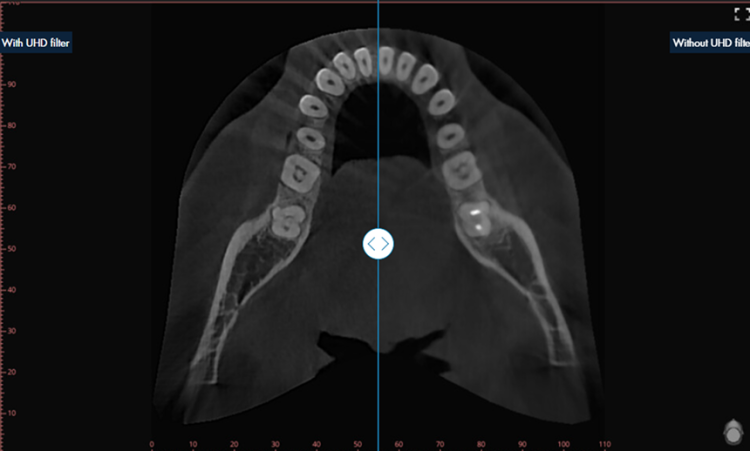

UHD Filter powered by AI

The UHD filter adjusts the brightness and contrast of the X-ray image individually and dynamically in different image areas. The result is an optimized X-ray image that enables clear and precise diagnostics. The filter is available for intraoral, panoramic, ceph and 3D/CBCT images.